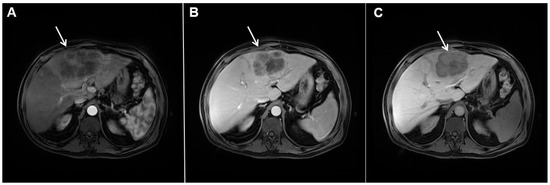

Mass-forming ICC typically presents as a large, lobulated, irregularly shaped lesion with well-defined borders [14]. On MRI, the tumor is usually hypointense on T1-weighted images, while the appearance on T2-weighted images varies from hypointensity in highly fibrotic lesions to hyperintensity in necrotic or mucin-rich tumors [15]. Although central T2-weighted hypointensity is considered a characteristic MRI feature of mICC, it can also be seen in colorectal metastasis due to intralesional coagulative necrosis [14]. Nevertheless, in most of the cases mICC presents as a heterogeneous lesion on T2-weighted images containing both areas of hyperintensity and areas of hypointensity [14,15]. The characteristic enhancement pattern using conventional gadolinium-based extracellular agents consists of an irregular ring enhancement on the arterial phase followed by progressive central enhancement in the portal venous and delayed phases (Figure 1) [14,15]. This postcontrast behavior could be explained by a rim of viable cells at the periphery of the tumor and rich edematous internal fibrous stroma [15].

Figure 1.

Typical intrahepatic mass-forming cholangiocarcinoma in 68-year-old woman. On axial T2-weighted image a lobular heterogeneously hyperintense tumor (arrow) is seen, located centrally in the liver segment IVB (A). The lesion (arrow) is hypointense in a plain T1-weighted image (B) with irregular ring enhancements in the arterial phase (C) and progressive enhancement in the portalvenous (D) and delayed phase (E). Note the perilesional biliary dilatation. Hematoxylin and eosin (H&E) staining (F) showed cholangiocarcinoma (arrow) and normal liver parenchyma next to the tumor (dashed arrow); original magnification ×40.